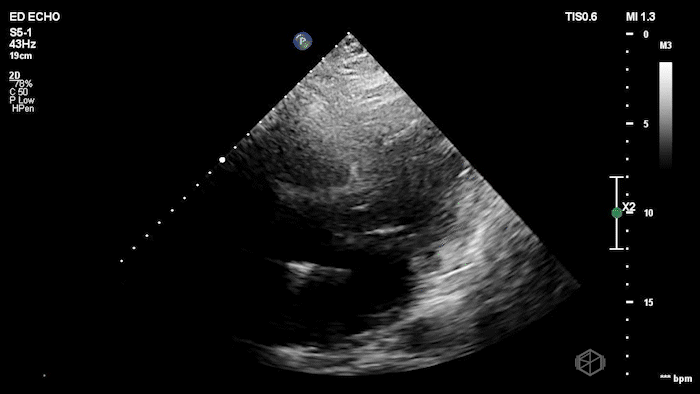

01 - What is the concerning finding and what is the differential?

Mitral valve mobile echogenic mass concerning for endocarditis, patient found to have MV endocarditis.